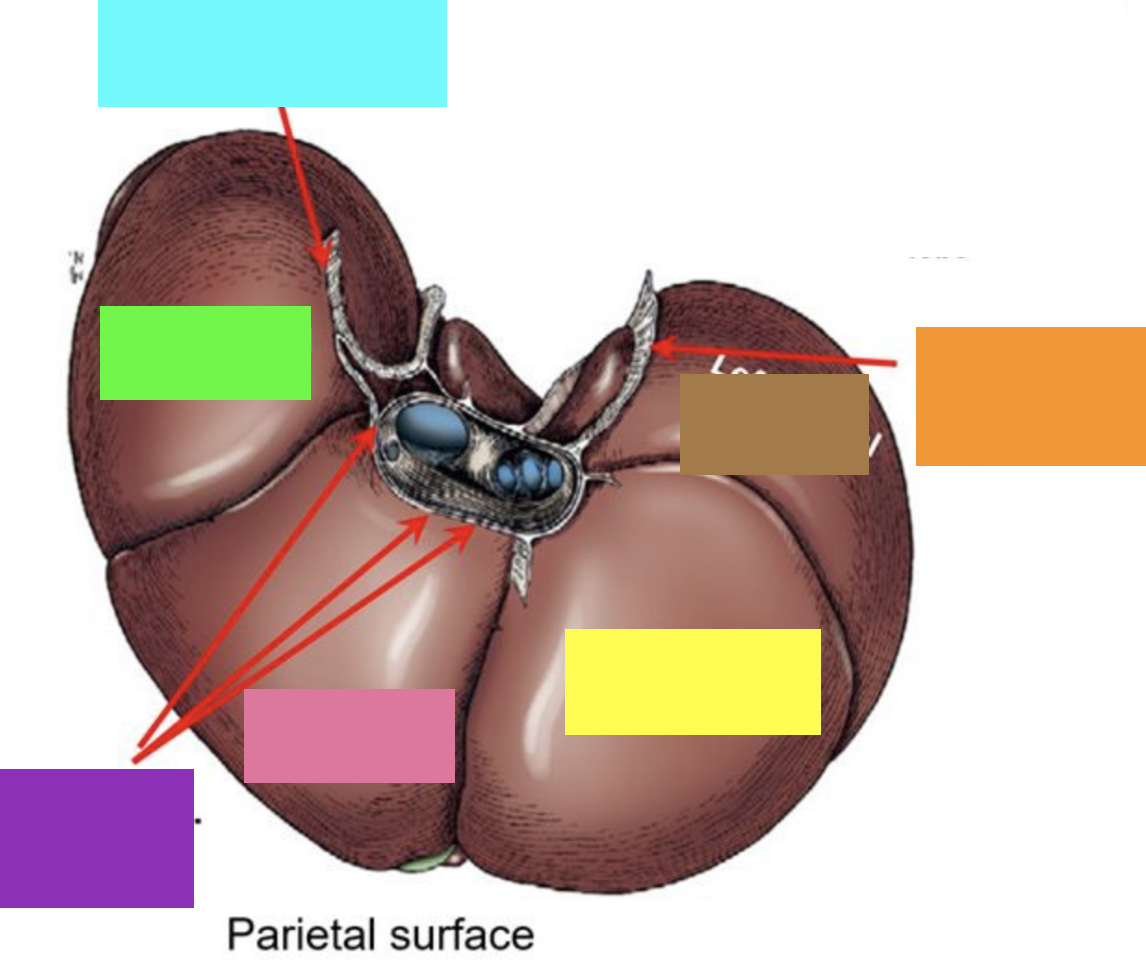

blue box

right triangular ligament

green box

right lateral lobe

purple box

coronary ligament

pink box

right medial lobe

yellow box

left medial lobe

orange box

left triangular ligament

brown box

left lateral lobe